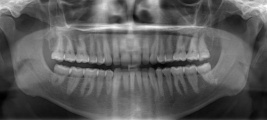

Dutina ústní a zuby

Dutina ústní obsahuje jazyk z kosterní svaloviny a zuby. Mléčný (dočasný) chrup člověka sestává z 20 zubů, trvalý ze 32 zubů. Každá ½ čelisti dospělého obsahuje 2 řezáky, 1 špičák, 2 třenové zuby a 3 stoličky. Zuby se člení na korunku (1), krček (2) a kořen(y) (3). Povrch korunky je kryt sklovinou (4), pod ní je zubovina (dentin, 5), uvnitř zubu je dřeň (6) s cévami a nervy. Kyseliny vytvářené bakteriemi mohou ničit tkáně zubu a zapříčinit vznik zubního kazu. Tomu je výhodné předcházet náležitou ústní hygienou.